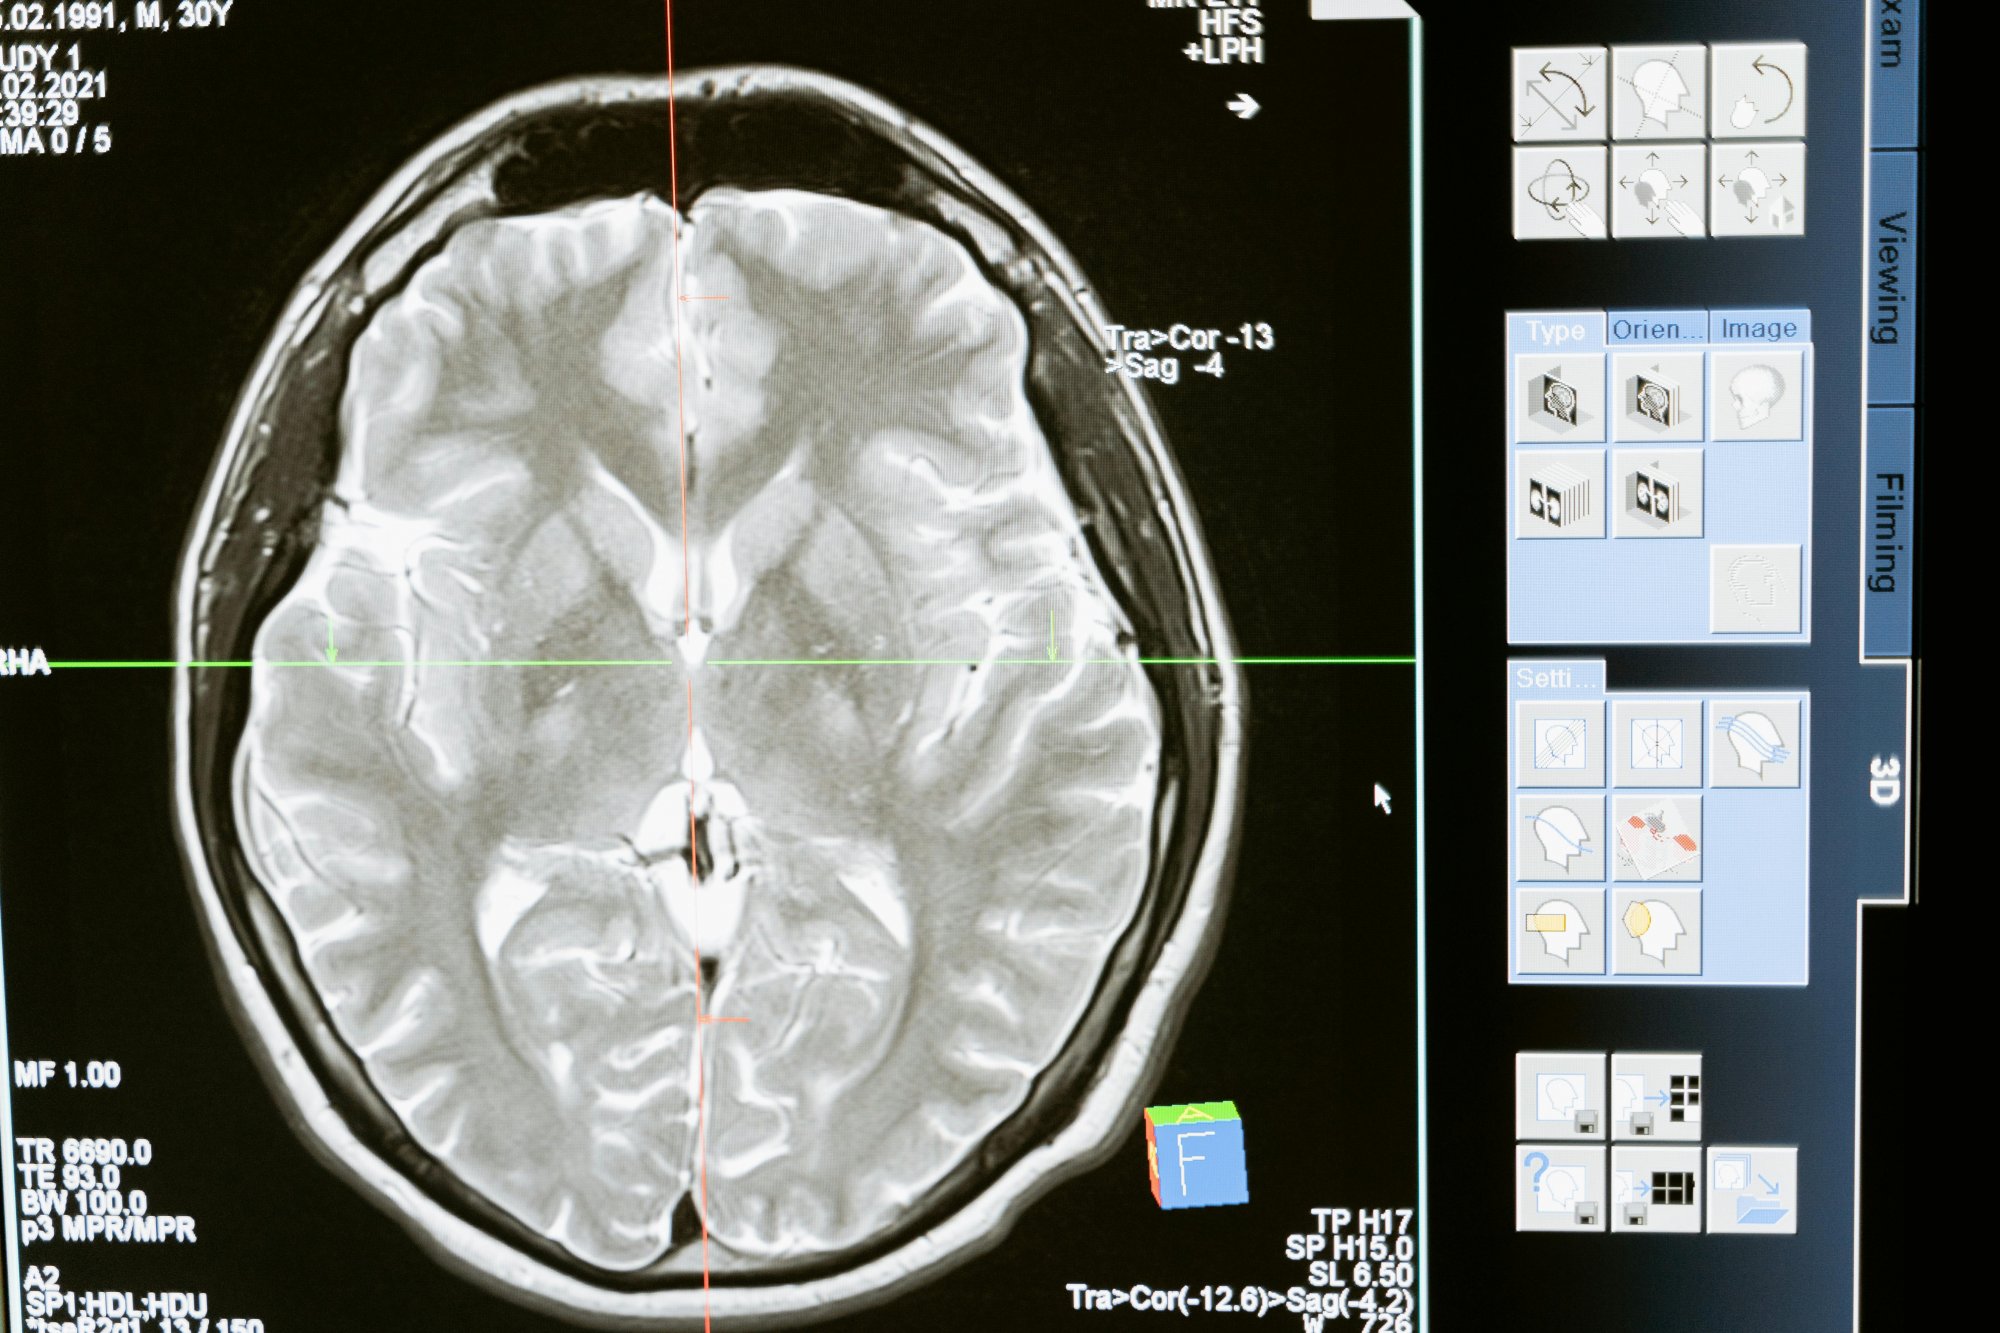

Έρευνα σε 26.000 άτομα διαπίστωσε ότι όσοι μένουν ξύπνιοι μέχρι αργά σημείωσαν καλύτερη βαθμολογία σε τεστ νοημοσύνης, συλλογισμού και μνήμης

Αποδείχτηκε ότι το να μένουμε ξύπνιοι μέχρι αργά θα μπορούσε να είναι καλό για την εγκεφαλική μας λειτουργία, καθώς η έρευνα δείχνει ότι οι άνθρωποι που χαρακτηρίζονται ως νυχτοπούλια θα μπορούσαν να είναι πιο οξυδερκείς από εκείνους που πέφτουν για ύπνο νωρίς.

Οι ερευνητές με επικεφαλής ακαδημαϊκούς του Imperial College του Λονδίνου μελέτησαν στοιχεία από τη μελέτη UK Biobank για περισσότερους από 26.000 ανθρώπους που είχαν συμπληρώσει τεστ νοημοσύνης, συλλογισμού, χρόνου αντίδρασης και μνήμης.

Στη συνέχεια εξέτασαν πώς η διάρκεια, η ποιότητα και ο χρονοτύπος του ύπνου των συμμετεχόντων επηρέαζαν τις εγκεφαλικές επιδόσεις.